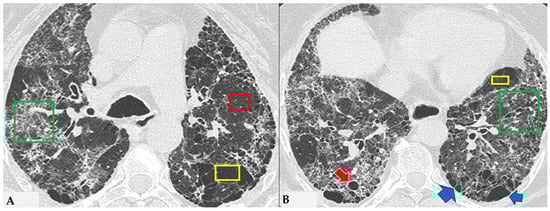

The fibrotic damage in HP is often more severe and extensive in the middle or middle-lower lung zones, but at times, it can be equally distributed across all three lung zones with relative sparing of the subpleural compartment, presenting a “patchy” distribution as a trace of a previous inhalation-mediated immune attack. This distribution may not always exhibit a clear central or peripheral predominance, as evident in axial assessments or MPR reconstructions [7,8,9]. The obstruction of small airways, another significant and distinctive feature of HP, can manifest with various characteristics. In (NFHP), poorly defined centrilobular nodules (fluffy nodules) and mosaic attenuation can be observed. The corresponding HRCT semiotics in FHP presents a “three-density pattern” (Figure 5), characterized by the simultaneous presence of pulmonary lobules with normal density, lobules with (GGO) and lobules with reduced density and size of vascular structures (mosaic attenuation/air trapping) due to air entrapment resulting from broncho-obstruction (Figure 6). The three-density pattern becomes more evident in expiratory HRCT scans due to the air entrapment resulting from the pathogenesis of bronchiole obstruction [4,10].

Figure 5.

FHP: chest HRCT ((A,B): axial scan). Visible is the “three density pattern”, with areas of the lung with normal density spared from pathological changes (red box); areas of the lung with reduced density characterized by a paucity of vascular and bronchial structures (yellow box); areas of the lung with increased density showing reticulations, interstitial thickening and traction bronchiectasis (green box). Lung cyst (red arrow) and areas of smoking-related paraseptal emphysema and advanced destructive emphysema (ADE) (blue arrows) are also present.